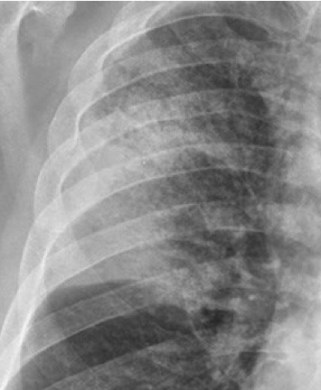

CASO: sospecha de neumonía.

Hallazgos:

- En un principio podríamos decir que existe un aumento de densidad retrocardiaco que podría ser compatible con condensación neumónica a dicho nivel, sin embargo estamos ante una placa poco inspirada, lo cual puede llevarnos a cometer errores diagnósticos.

- Se recomendó volver a realizar la radiografía, observar a continuación:

Ya no se observa el aumento de densidad retrocardiaco, la placa es normal.

INSPIRACIÓN: Una placa bien inspirada es aquella en la que se observar 6-7 arcos costales anteriores o 10-11 arcos costales posteriores. Lo contrario puede producir imágenes falsas de condensaciones o de seudocardiomegalia.